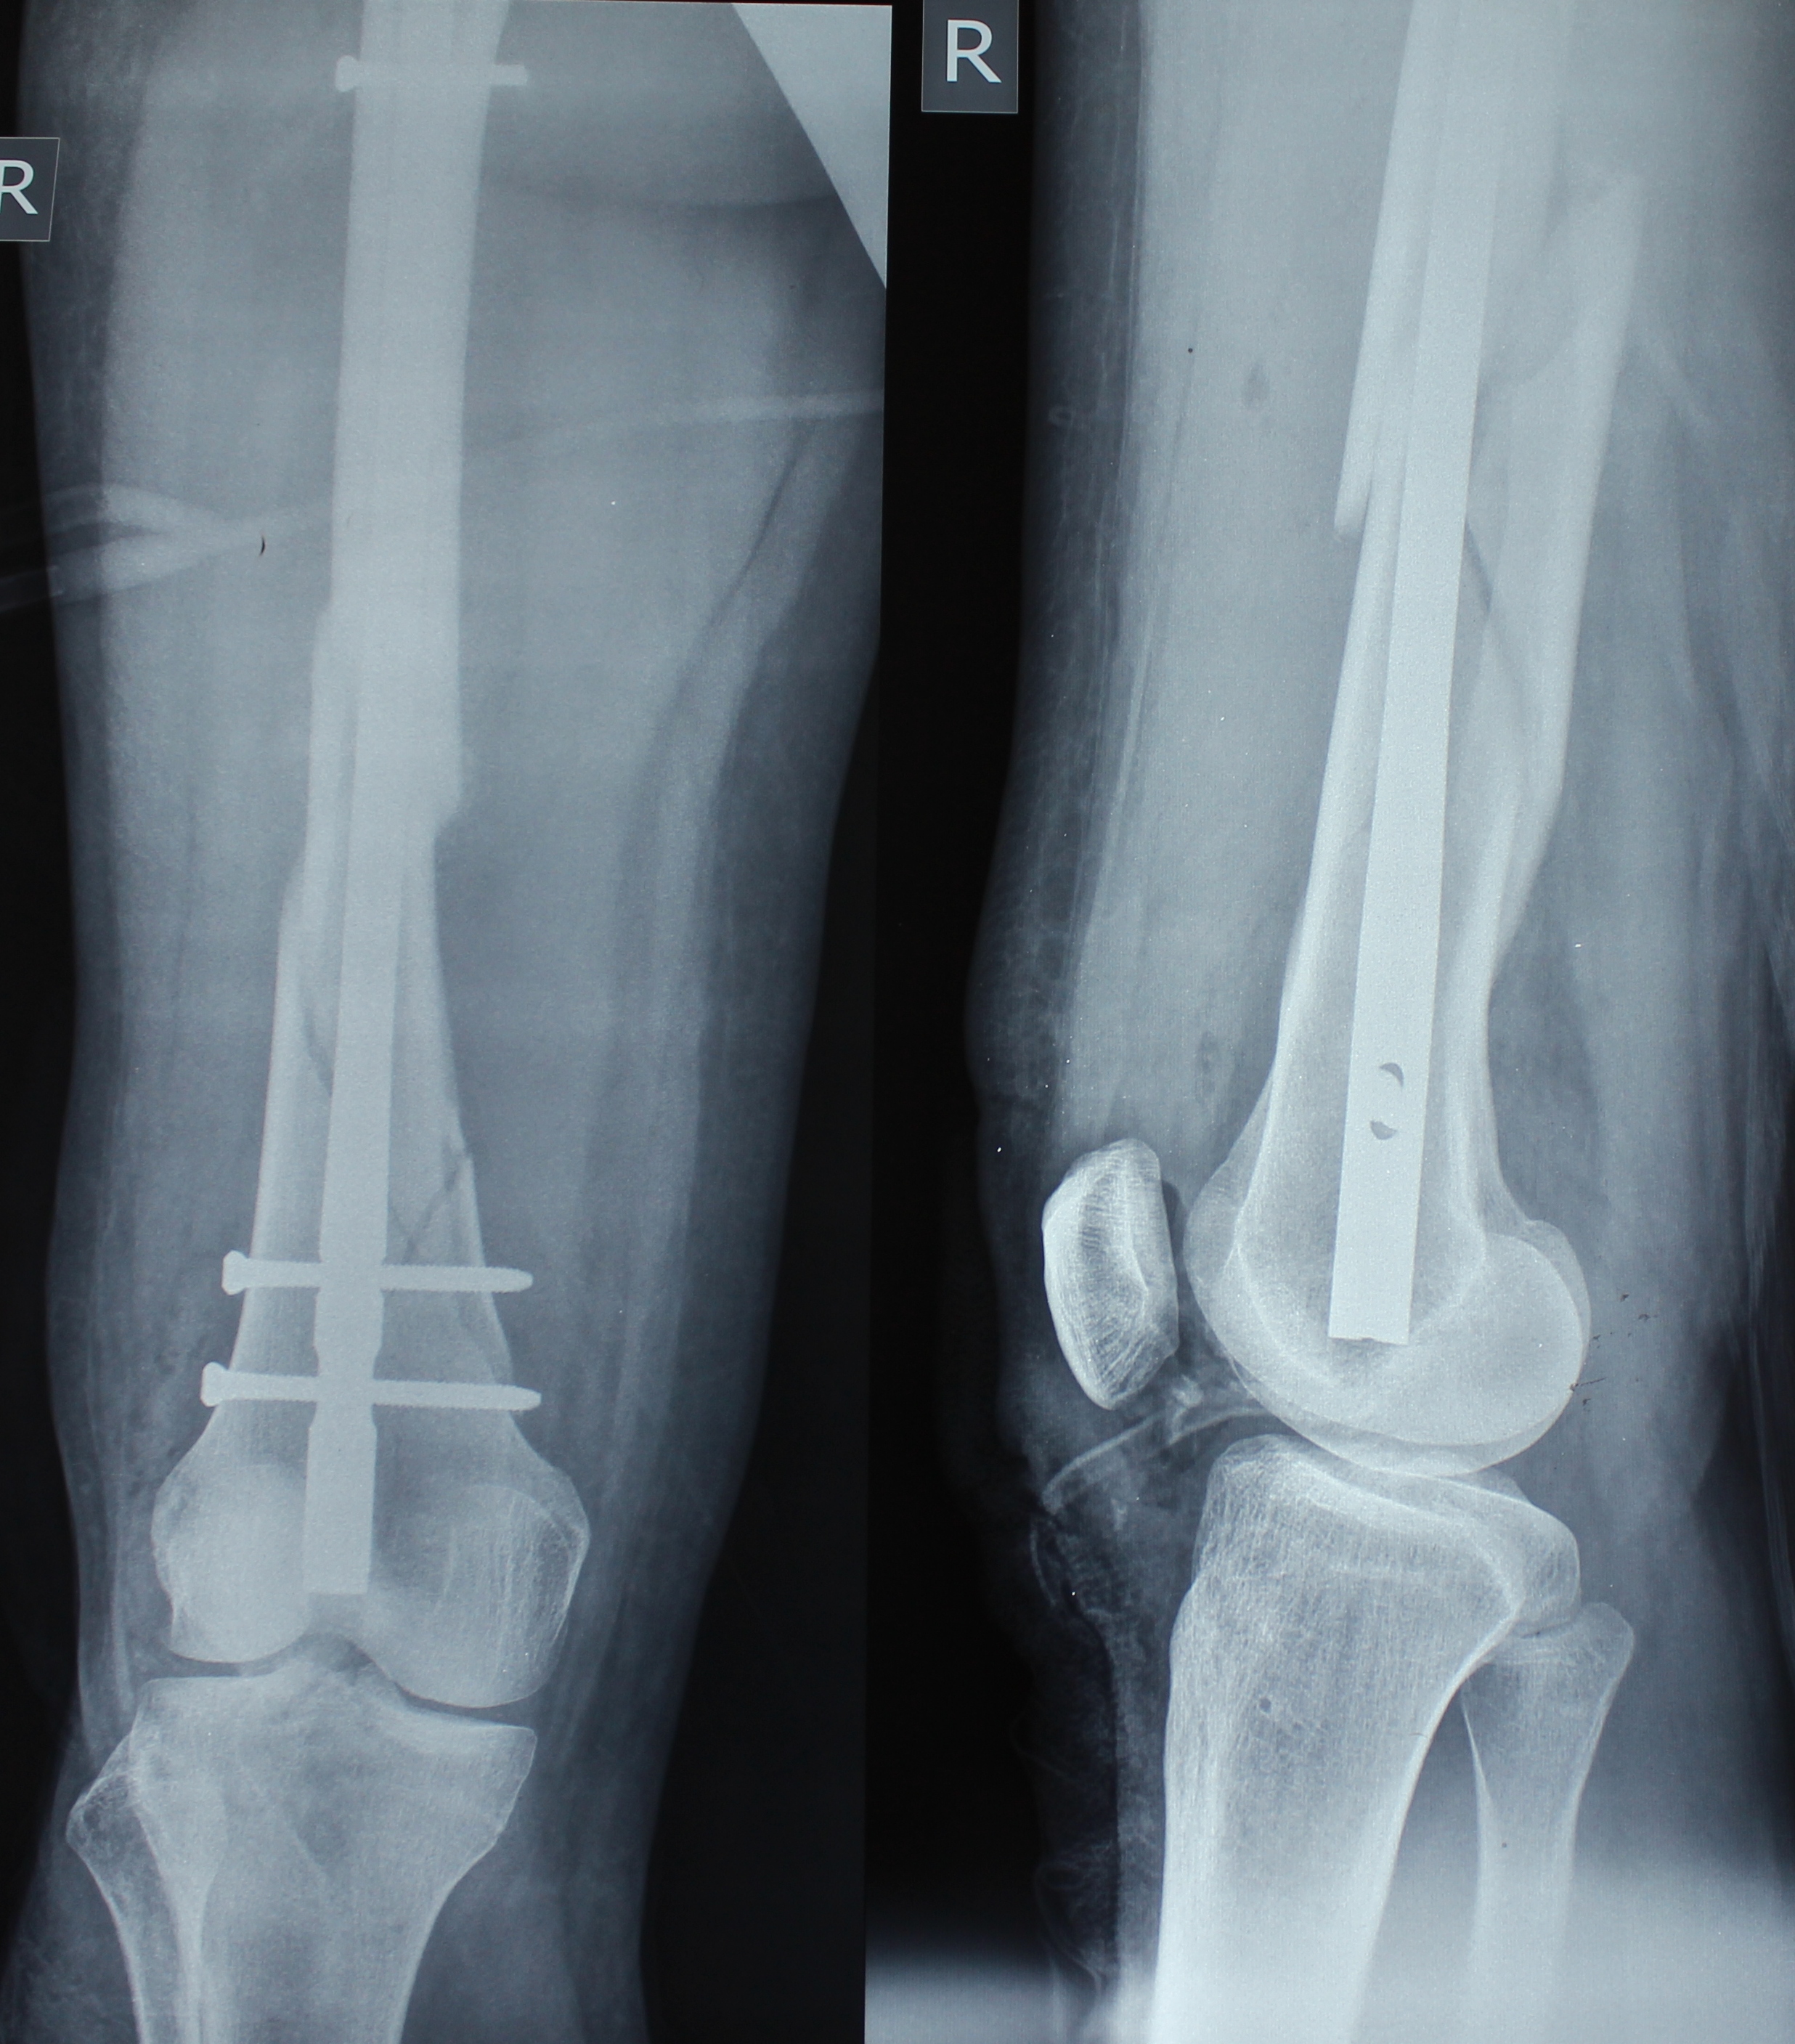

Специалисты РКБ с согласия Веры, находящейся на 36 неделе беременности, сделали ей рентген и поставили диагноз «многооскольчатый перелом бедренной кости на протяжении от нижней трет и до средней трети с крупными фрагментами».

- Малоинвазивным доступом – то есть через минимальные сантиметровые разрезы трансартикулярно (через коленный сустав) выполнена закрытая репозиция и блокирующий интрамедуллярный остеосинтез стержня. Простым языком - женщине в канал кости вживили титановый стержень диаметром 10 мм и длинной 34 см и зафиксировали специальными винтами,- пояснил врач-травматолог.